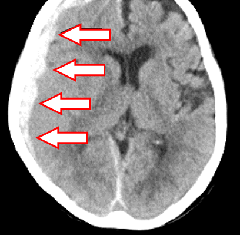

(下図1)右被殻出血で突然の左半身のまひが起こった症例です。

(下図2)脳皮質下での出血が脳室まで広がった脳室穿破の症例です。

右被殻出血

脳皮質下出血

脳内出血

高血圧が原因となり、もろくなった脳内の小血管に動脈瘤が破れて脳内に出血します。出血の部位やサイズによって、開頭血腫除去術・定位血腫吸引術や脳室ドレナージ術などが行われます。